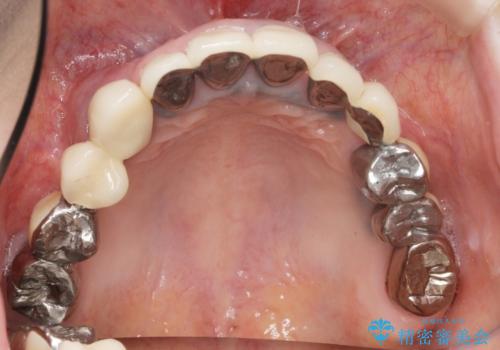

全顎的 虫歯治療 インプラント補綴

- 患者様

- 50代女性

- 治療期間

- 3年

- 治療回数

- 10-30回

今後延々と治療を繰り返さないために、全ての銀歯を外し虫歯を丁寧に取り切り、根管治療を行い、残せない歯は抜去を行った上でインプラント治療を行っていくことで全体的な治療を計画していくこととなりました。

- 費用(概算)

- 440万円費用は治療当時の料金となります